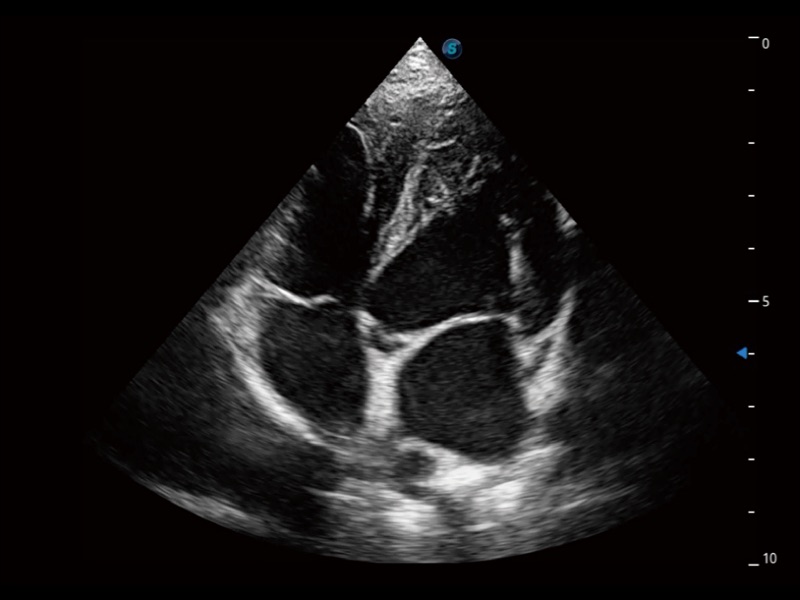

(犬)四腔心

(犬)四腔心MQA

• AMM 解剖M型

通过360度任意调节3条M型取样线,在同一心动周期上观察心脏不同位置的运动曲线,得到准确的心功能测量数据,有效评估心肌运动及左心室功能。